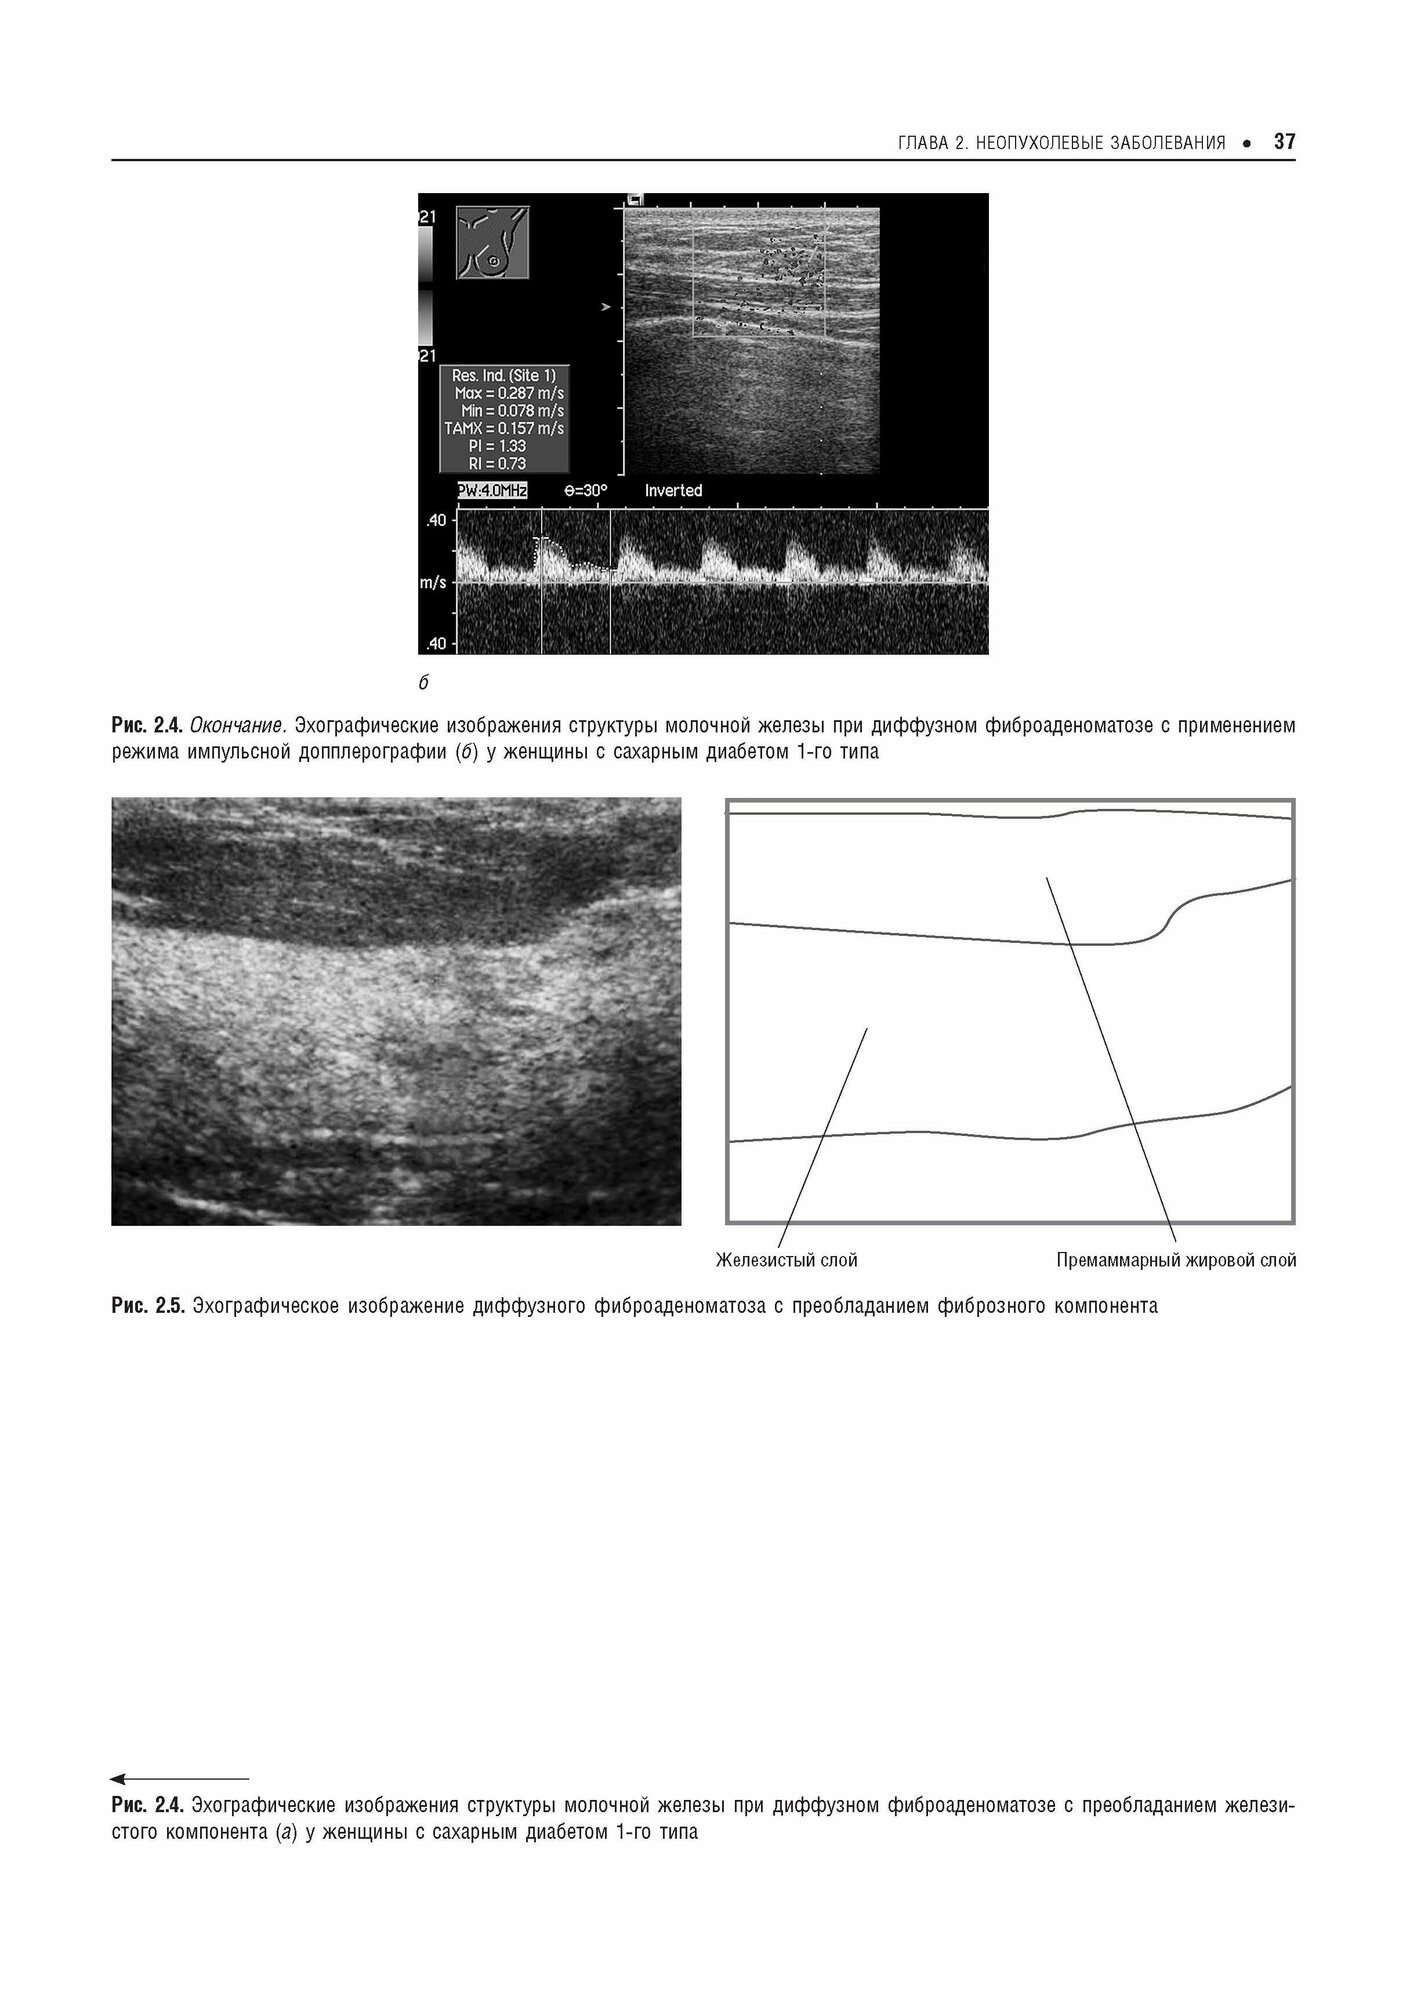

Практическая ультразвуковая диагностика. Руководство для врачей в пяти томах. Том 5. Ультразвуковая диагностика заболеваний молочных желез и мягких тканей (Труфанов Геннадий Евгеньевич, Иванова Людмила Игоревна, Вецмадян Елена Анатольевна); ГЭОТАР-Медиа, 2017

Пятый том руководства посвящен использованию различных методик ультразвукового исследования в диагностике заболеваний молочных желез и мягких тканей.

.Первая часть книги посвящена ультразвуковым исследованиям молочных желез. Описаны нормальная ультразвуковая анатомия, клинические особенности и ультразвуковая семиотика наиболее часто встречающихся заболеваний и патологий. Отдельная глава дает обзор методов и методик компрессионной эластографии в маммологии.